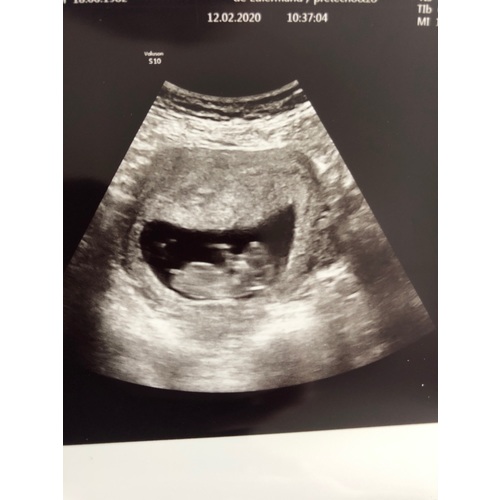

Wij hebben vrijdag de 20weken echo en dan hopen we ook te horen wat het wordt. Willen jullie alvast een gokje wagen om te zien of jullie gelijk zullen hebben? Dit was een echo van 16 weken